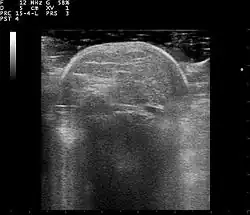

Lipoma ultrasound 110322120428 1206550

Familial multiple lipomatosis is usually diagnosed through a physical exam via palpation, medical history and imaging studies such as ultrasound, CT scan, or magnetic resonance imaging (MRI). A CT scan is an imaging method that uses x-rays to create images of cross sections of the body, while an MRI uses powerful magnets and radio waves to create images of lipomas and surrounding tissues.[3] Both tests are useful to establish the diagnosis of multiple symmetric lipomatosis, although magnetic resonance imaging provides more details and may be used when lipomas are large, deep, or have infiltrated muscle fibers or nerves. In some cases, a biopsy of the lipomas may be necessary to confirm the diagnosis.[3]